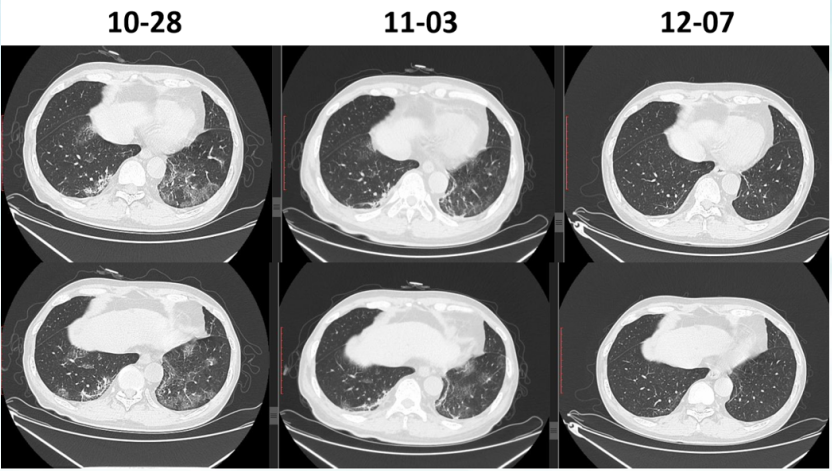

1CMV肺炎:单纯的CMV肺炎比较罕见,笔者中心1000多例移植患者仅有2例发生CMV肺炎。其中1例患者肾移植术后1月余,发热1天。影像学可见双肺弥漫性病变,多发结节(图12)CMV肺炎进展及恢复速度都很快(图13)

图片

13  患者治疗前后胸部CT变化